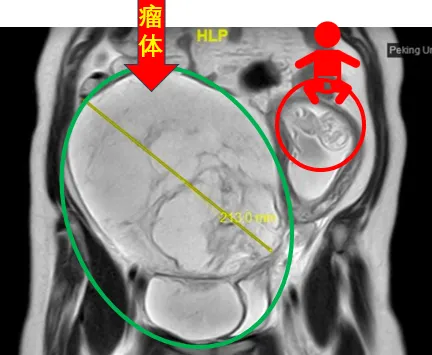

31歲的謝女士罹患靜脈內(nèi)平滑肌瘤病兩年多,正鼓起勇氣準(zhǔn)備接受治療時(shí),意外發(fā)現(xiàn)自己懷孕了。在孕期激素的“加持”下,謝女士盆腔內(nèi)的瘤體迅速增大至足月胎兒大小,血管內(nèi)瘤栓沿著右側(cè)髂靜脈、下腔靜脈一直“爬”到右心房,甚至在心臟舒張期進(jìn)入右心室,使她處于隨時(shí)可能猝死的高危風(fēng)險(xiǎn)下。

▲2024年4月,謝女士的核磁共振圖像顯示,巨大腫瘤將她的子宮擠到了腹腔左側(cè)